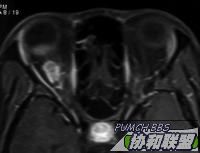

患者女性30岁。主诉右眼视力下降半年。检查右眼视力眼前手动,眼前节正常。眼底见后极部颞侧实性隆起,周边浅层网脱。超声及MRI见图。全身检查未发现明显异常。

MRI  T1 & T2

图片点击可在新窗口打开查看